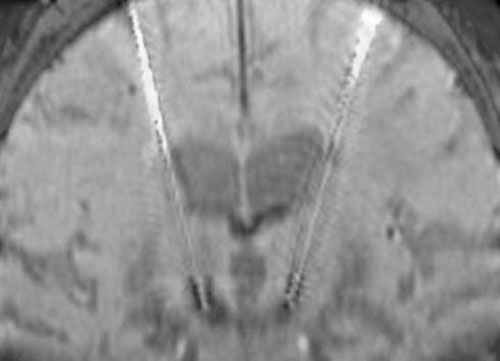

以周东主任为首的神经外科治疗团队,对李伯进行术前详细评估,符合DBS手术标准。手术由神经外科周东主任和秦琨主刀。首先定位好脑内需要刺激的核团靶点,然后通过立体定向头架,从额叶切两个口入路,将刺激电极放置入目标核团,再将电刺激器放入脑内靶点。能否精准的将电极放入脑内的目标位置,是决定该手术成败的关键因素。以往放置电极主要通过立体定向专用头架在MR和CT的帮助下完成,操作比较繁复。目前,神经外科将O臂引入整个手术操作流程,在放置电极的过程中,进一步明确了刺激器电极的位置,也确认了颅内的基本情况,提高了手术精确性和安全性,同时也使手术更为顺畅。

DBS手术非常顺利,手术中按照预选的核团,精准的将电极放入脑内的靶点,同时再用O臂和导航系统进一步证实了电极准确的放置于目标神经核团。